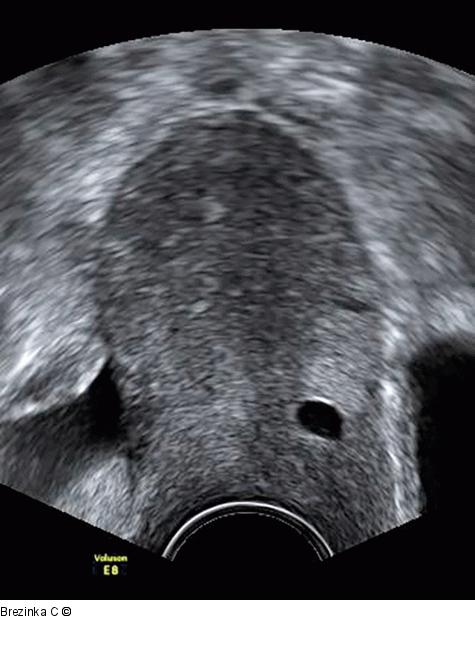

Abbildung 3: Ovulum Nabothii Ein 6 mm großes Ovulum Nabothii auf der Höhe des Übergangs Zervix-Corpus uteri. Die echoleere Zyste verursacht das Artefakt der distalen Schallverstärkung. |

Ein 6 mm großes Ovulum Nabothii auf der Höhe des Übergangs Zervix-Corpus uteri. Die echoleere Zyste verursacht das Artefakt der distalen Schallverstärkung. |